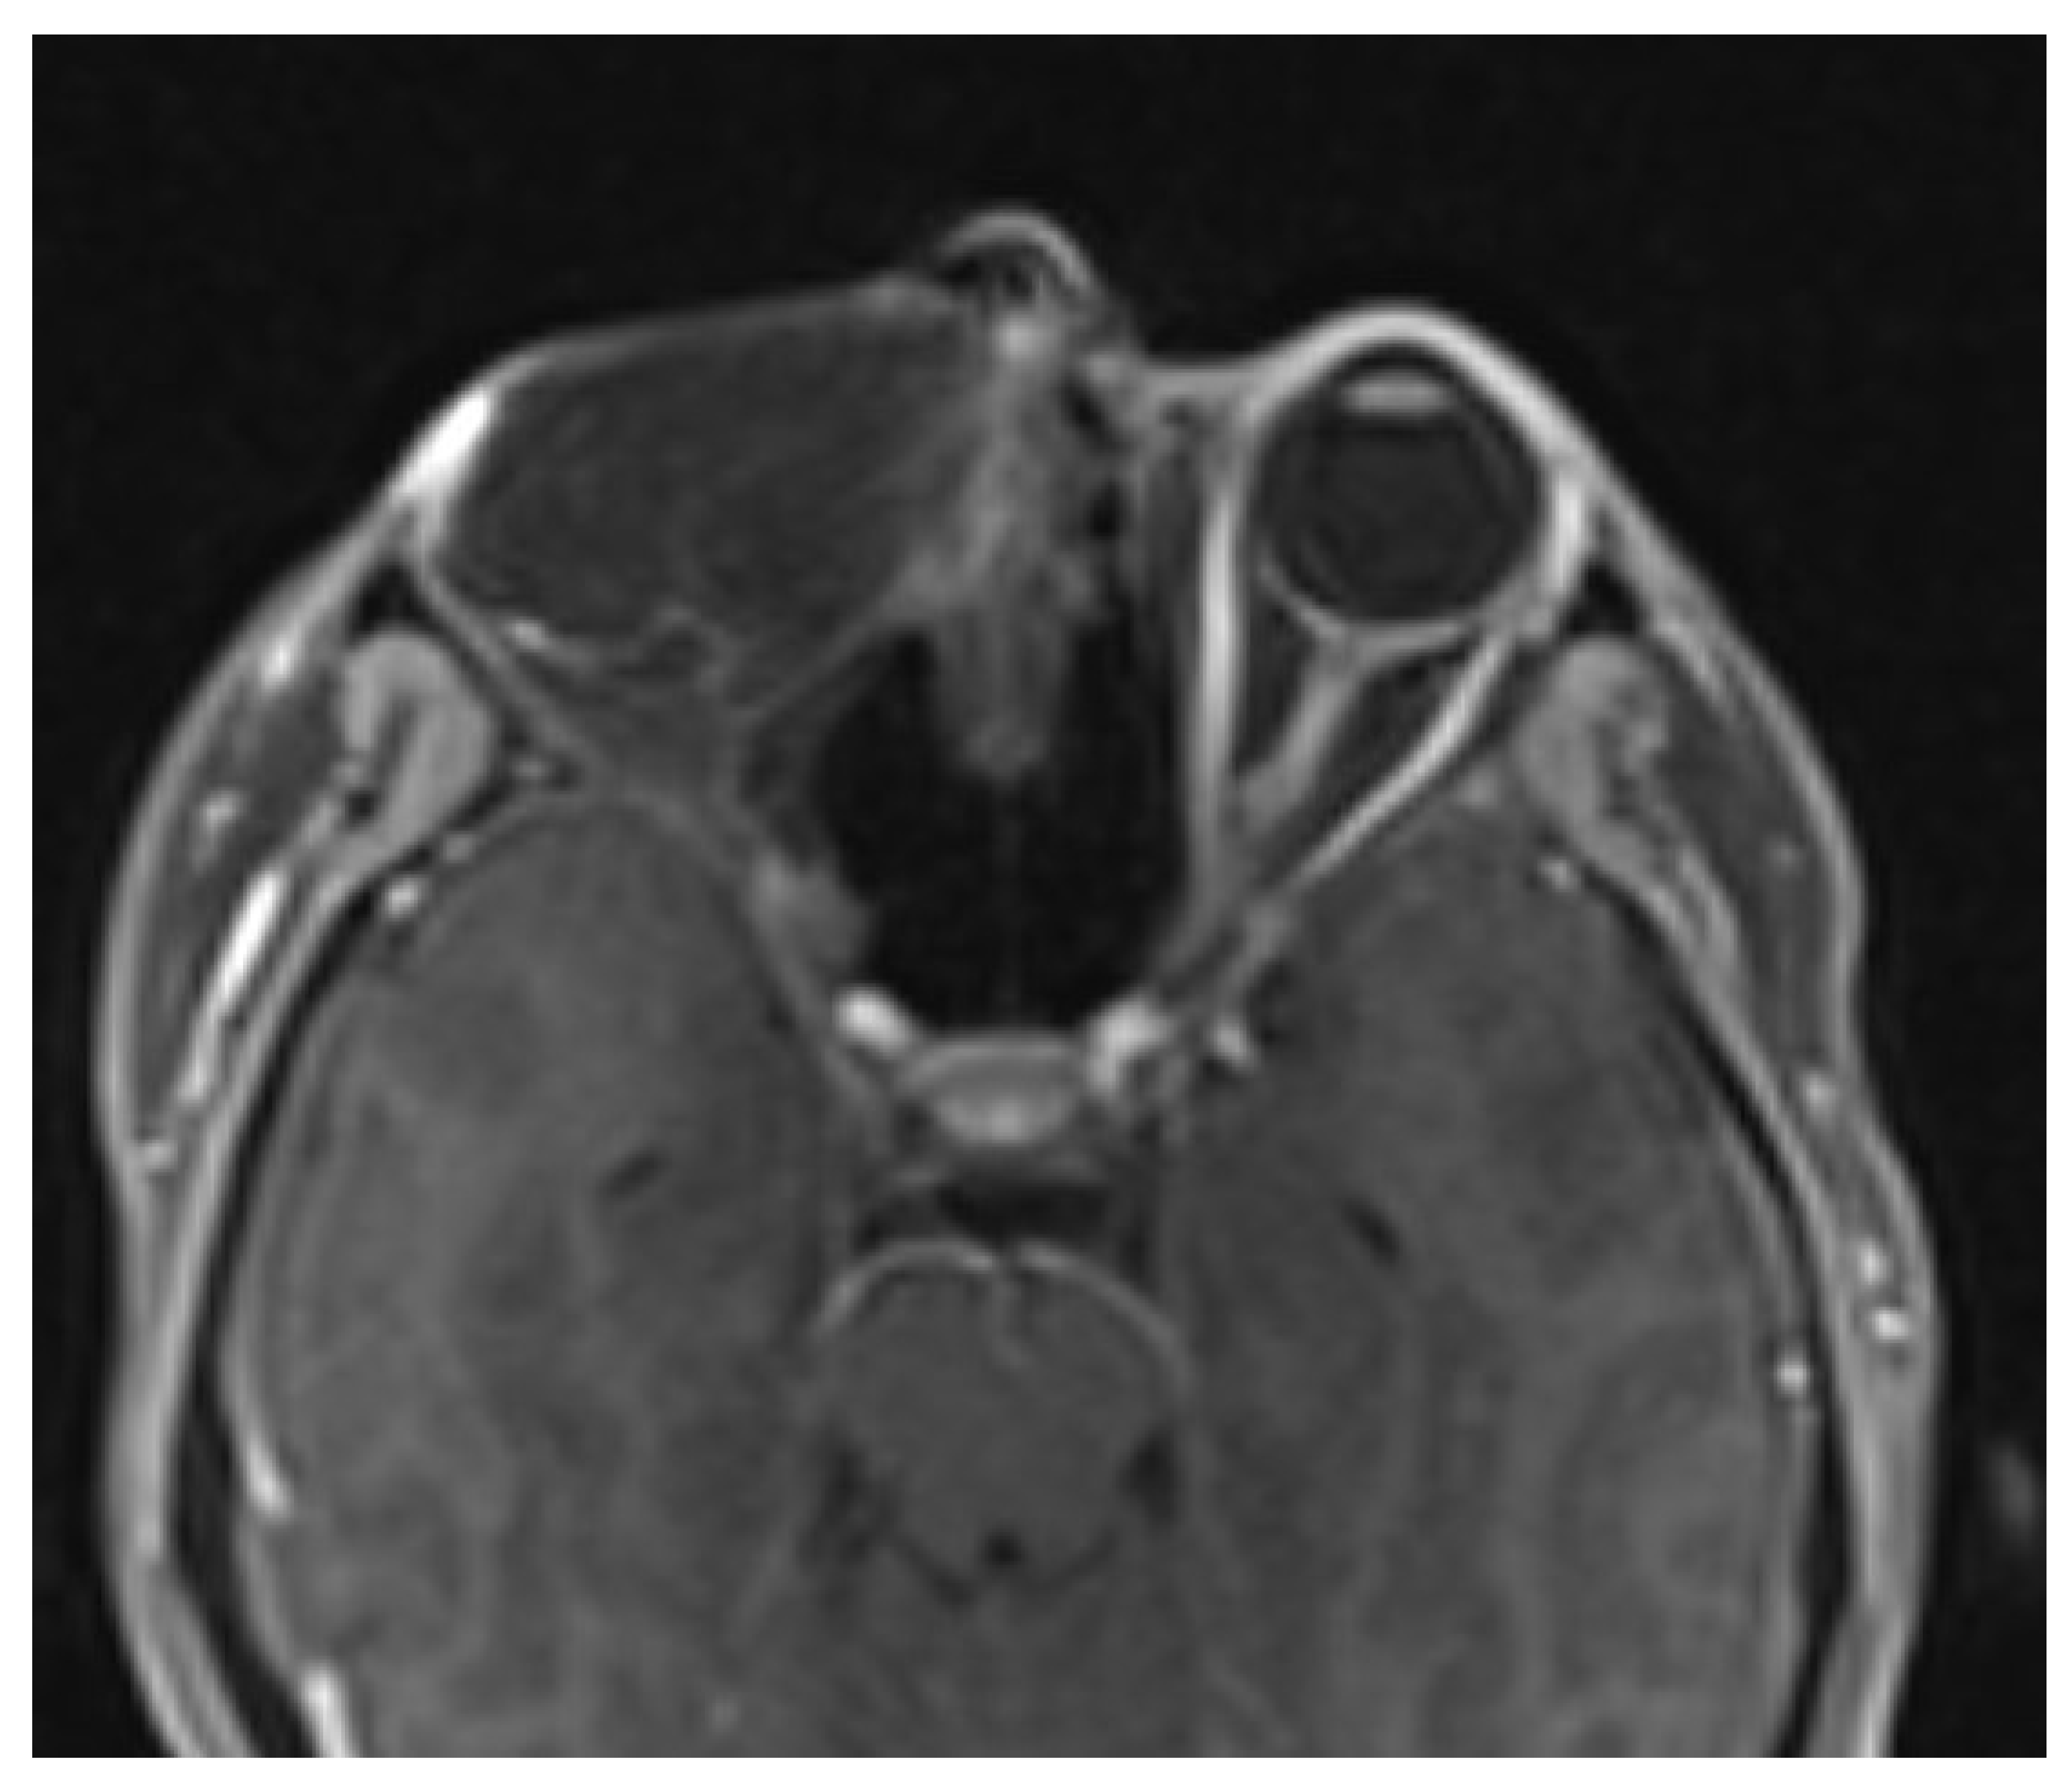

2. Case Presentation